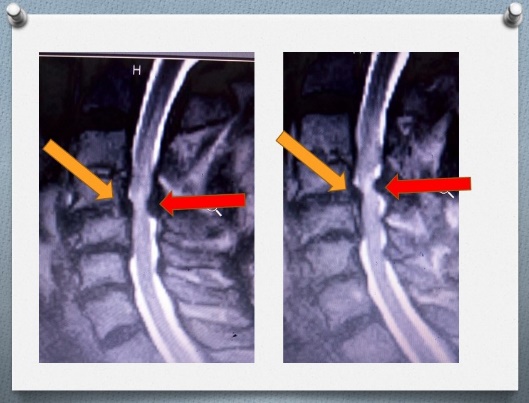

MRI SCAN SHOWING PROBLEM AREAS

Mr John had this problem and did an MRI scan. This is the gold standard test for cervical myelopathy. Ordinary x-rays can show the bones that are wobbly but MRI scan shows how the spinal cord is being affected and where. The MRI scan shows which junction is affected and by what. I hope you are following this analogy carefully.Â

The pressure and damage to the spinal cord was evident in Mr John. However, the pressure was from the front and back of the neck. This is like having the police and Civil Defence checkpoints in the same area!